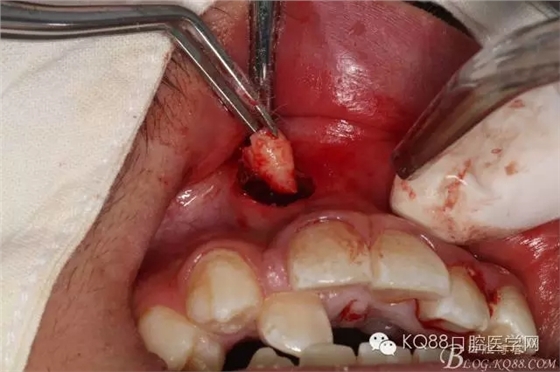

圖5.經(jīng)過仔細(xì)認(rèn)真的術(shù)前CBCT影像檢查分析,考慮手術(shù)進(jìn)路及操作性,局部浸潤(rùn)麻醉下,遂從唇側(cè)前庭溝處做弧形小切口、翻瓣。渦輪鉆去骨后的臨床情形:完美的弧形切口。去除唇側(cè)的骨板、顯露出部分多生牙的牙根和少量牙冠,位置之高,令人吃驚、一定要注意11的牙根,防止損傷11根尖。